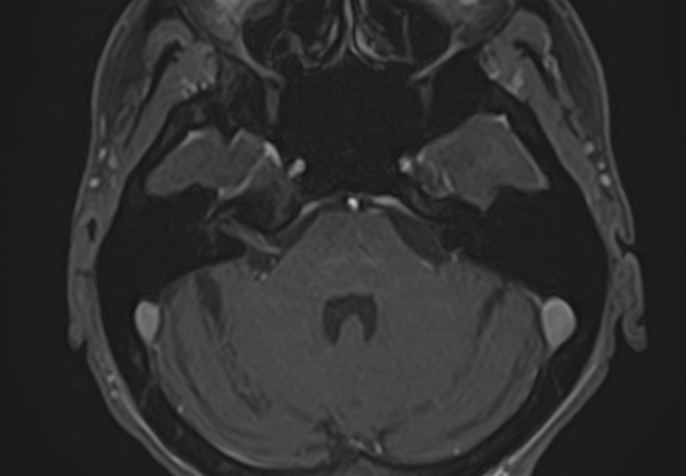

Внутреннее ухо – важная часть слуховой и вестибулярной систем тела человека, находящаяся в толще пирамиды височной кости.

Внутреннее ухо содержит слуховой орган (улитку) и орган равновесия (преддверие и полукружные каналы), патологические изменения которых в свою очередь приводят к развитию нейросенсорной тугоухости и вестибулярных нарушений.